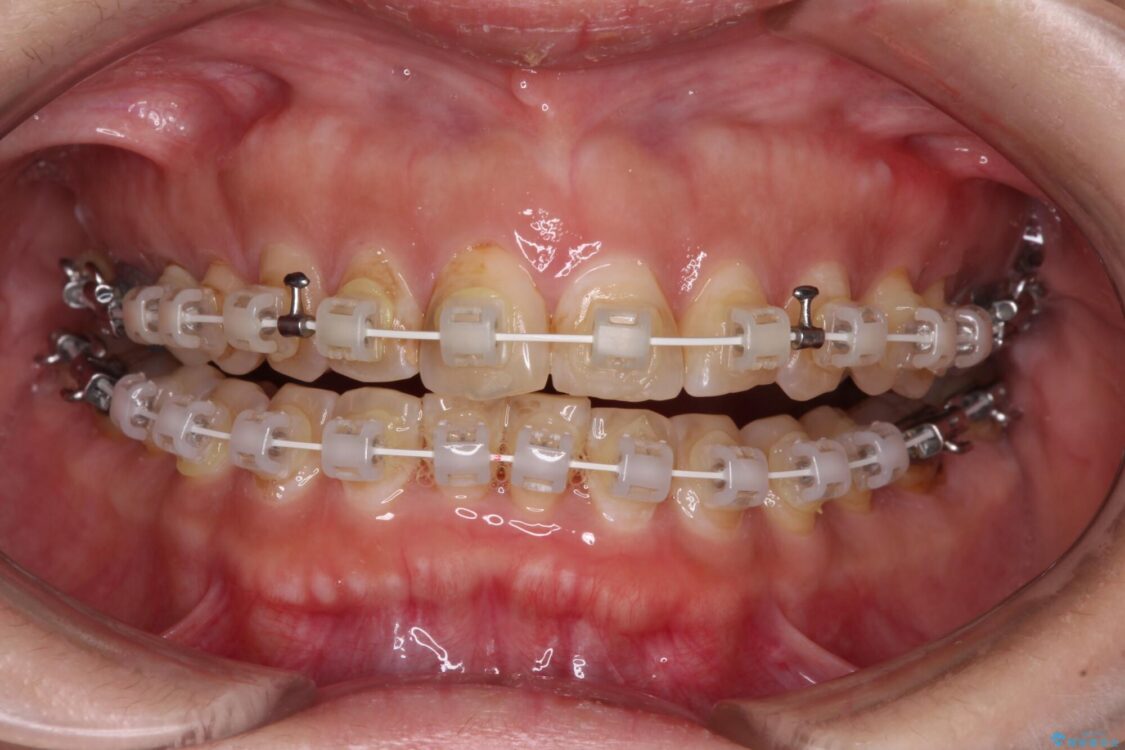

なるべく早めに治療を終えたいとのことで、補助装置を用いて上顎臼歯を後方に移動させ、同時にワイヤー装置にて整えることとしました。

舌の突出癖が原因で上下の歯に大きなスペースが生じていたため、舌のトレーニングをしっかり行っていただくことで、上顎歯列をスムーズに移動させることができました。

治療途中